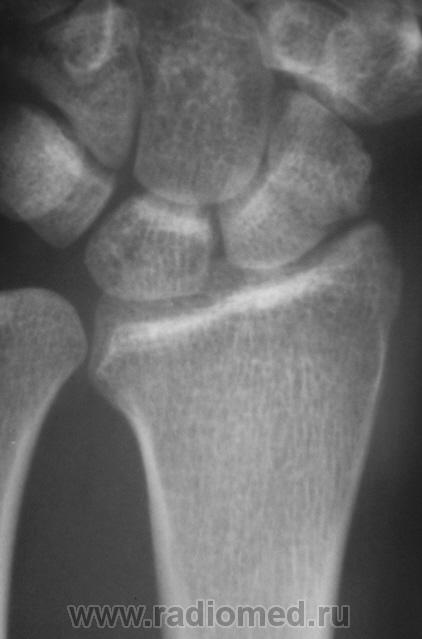

Катенёв Валенти... Дата публикации 15.10.2009, 20:32 Травма неделю тому. Пациент направлен на рентгенологическое исследование лучезапястного сустава с диагнозом "Перелом". Произведено исследование. Ваше мнение коллеги? Чт, 15/10/2009 - 20:36 #1 В.Б. Серов Не на сайте Был на сайте: 3 недели 3 дня назад Зарегистрирован: 16.07.2008 - 10:15 Публикации: 1376 Нужен косой снимок, подтвердить/опровергнуть перелом ладьи. Зри в корень! Чт, 15/10/2009 - 21:37 #2 Наталия Не на сайте Был на сайте: 9 лет 2 недели назад Зарегистрирован: 30.07.2008 - 13:24 Публикации: 538 Перелом ладьевидной кости без смещения виден хорошо. Чт, 15/10/2009 - 21:53 #3 Катенёв Валенти... Не на сайте Был на сайте: 7 лет 5 месяцев назад Зарегистрирован: 22.03.2008 - 22:15 Публикации: 54876 Да. линия перелома в ладьевидной кости, весьма хорошо дифференцируется

Перелом ладьевидной кости без смещения виден хорошо.

Да. линия перелома в ладьевидной кости, весьма хорошо дифференцируется